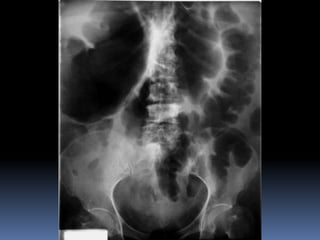

PROYECCION SIMPLE DE

ABDOMEN

CRITERIOS DE EVALUACION

P.S.A.

 Apreciar desde el

abdomen superior hasta

la sínfisis del pubis.

 Lumbares, pelvis y

ultimas costillas sin

rotación.

 Apófisis espinosas en el

centro de cuerpos

vertebrales.

 Ver el bazo, riñones,

psoas y “borde inferior

hepático

INTERPRETACION

 Estructuras óseas

(densidades).

 Tejido blando

 Psoas.

 Bazo

 Niveles Hidroareos.

 I.D.

 Colon

 Silueta Renal

CRITERIOS DE EVALUACION P.S.A.  Apreciar desde el abdomen superior hasta la sínfisis del pubis.  Lumbares, pelvis y ultimas costillas sin rotación.  Apófisis espinosas en el centro de cuerpos vertebrales.  Ver el bazo, riñones, psoas y “borde inferior hepático

INTERPRETACION  Estructuras óseas (densidades).  Tejido blando  Psoas.  Bazo  Niveles Hidroareos.  I.D.  Colon  Silueta Renal